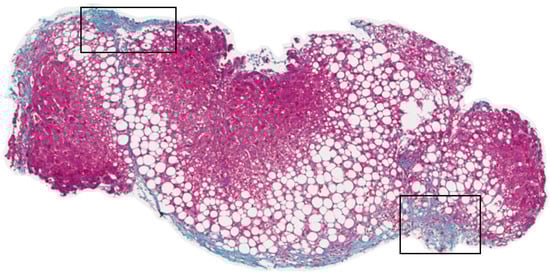

- Giannakeas, N.; Tsipouras, M.G.; Tzallas, A.T.; Kyriakidi, K.; Tsianou, Z.E.; Manousou, P.; Hall, A.; Karvounis, E.C.; Tsianos, V.; Tsianos, E. A clustering based method for collagen proportional area extraction in liver biopsy images. Proc. IEEE Eng. Med. Biol. Soc. Annu. Conf. 2015, 2015, 3097–30100. [Google Scholar] [CrossRef]

- Tsipouras, M.G.; Giannakeas, N.; Tzallas, A.T.; Tsianou, Z.E.; Manousou, P.; Hall, A.; Tsoulos, I.; Tsianos, E. A methodology for automated CPA extraction using liver biopsy image analysis and machine learning techniques. Comput. Methods Progr. Biomed. 2017, 140, 31–68. [Google Scholar] [CrossRef] [PubMed]